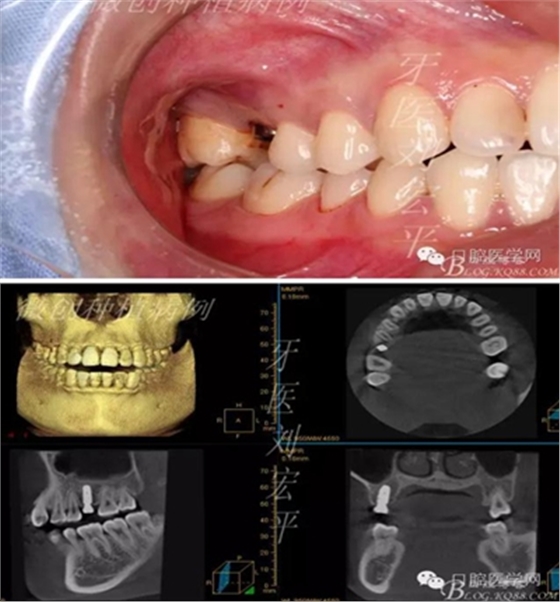

咬合照片

術(shù)前CT截圖,種植區(qū)骨高度及寬度充足